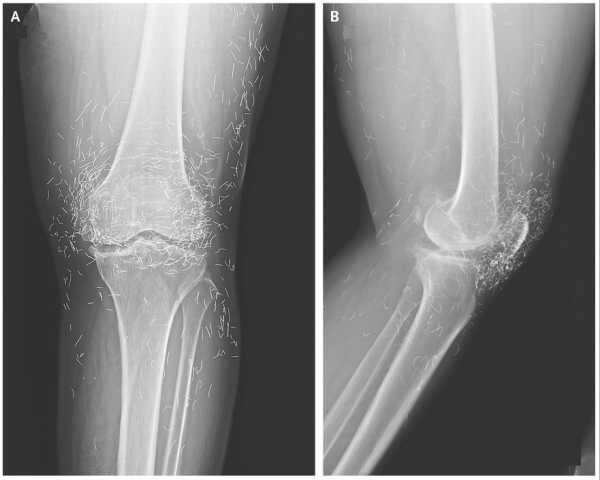

Симптоми: Пацієнтка протягом кількох тижнів відчувала задишку під час фізичної активності, коли звернулася до лікарні для обстеження. У неї також було в анамнезі виділення незвично темної сечі, що відбувалося з дитинства, а у 40 років їй зробили повне ендопротезування кульшового та колінного суглобів з обох боків через артрит.

Кислота, що накопичується, перетворюється на «охронотичний пігмент», який по суті забарвлює тканини, де він накопичується, і зрештою кальцифікується або твердне. Багатьом людям з алкаптонурією потрібне ендопротезування суглобів, оскільки їхні суглоби кальцифікувалися, а у деяких людей це кальцифікування також впливає на серце. Так сталося з 65-річною жінкою.

Сильний біль у коліні жінки виявив «золоті нитки» в її суглобах